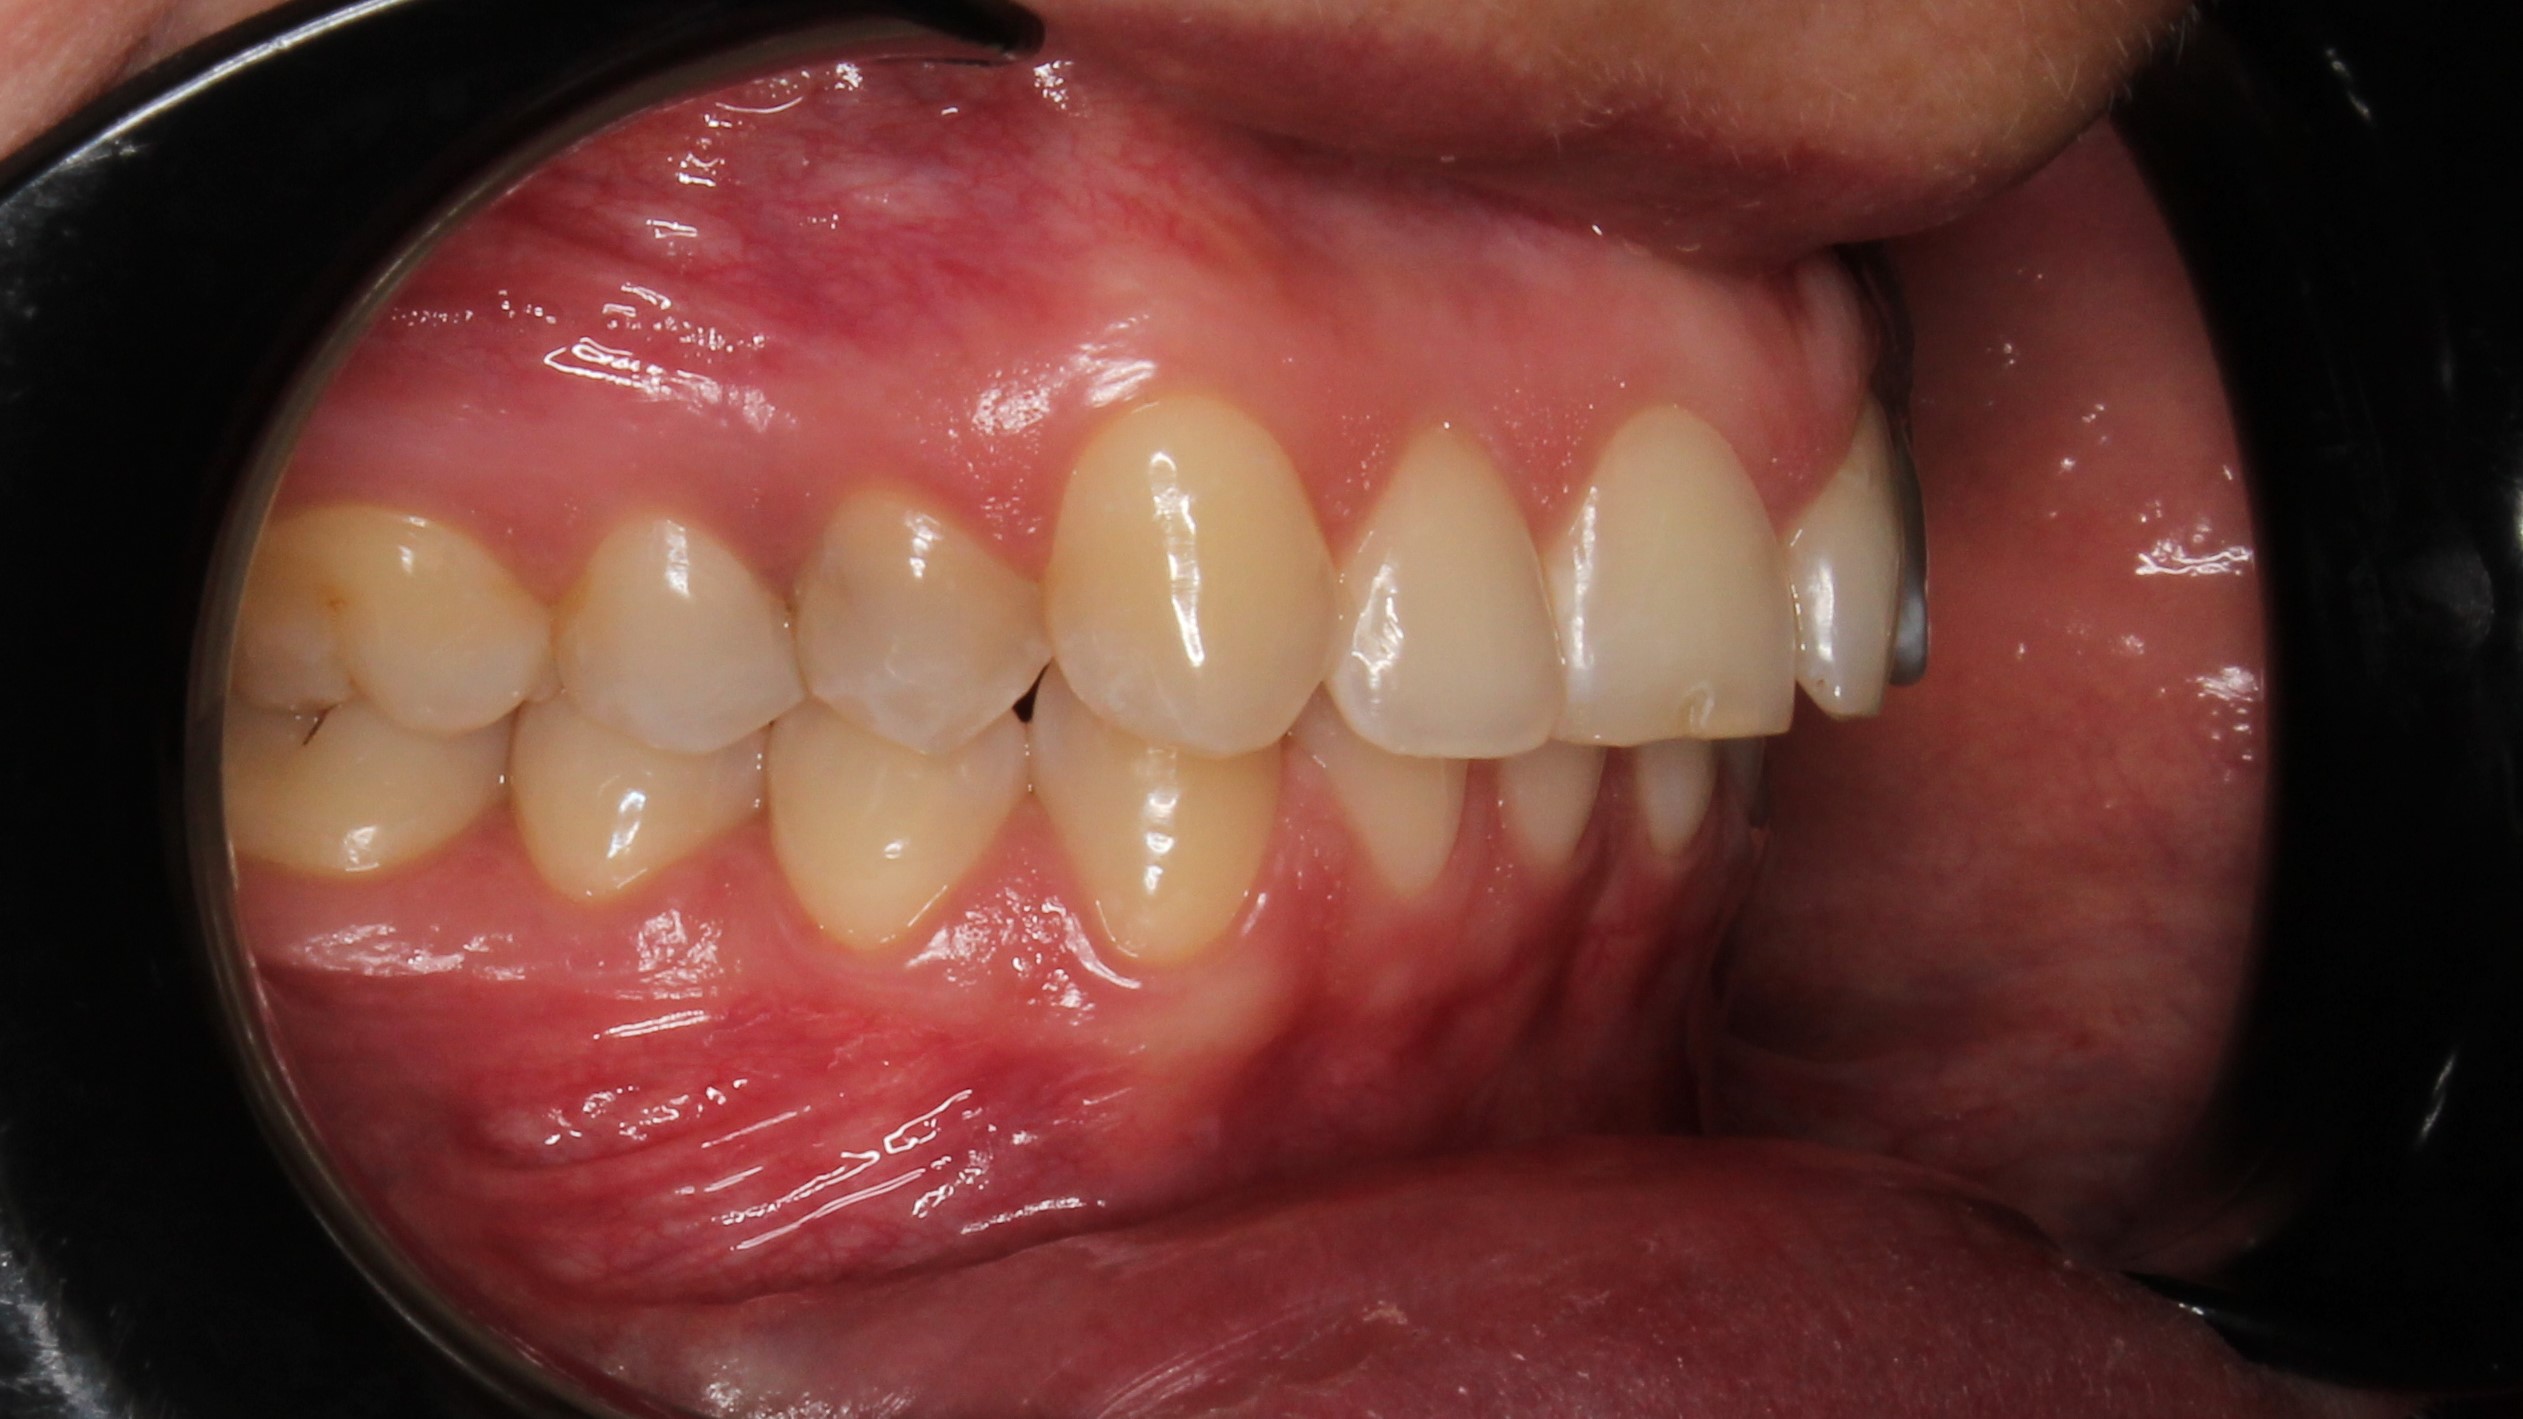

До и После: Лечение глубокого прикуса с помощью элайнеров Eurokappa